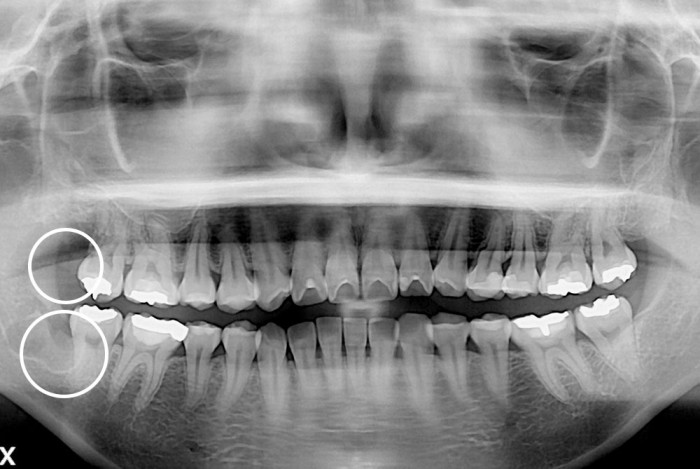

[사랑니] 사랑니

치료후 : 2019-10-23

세종치과는 구강악안면외과학 박사이신 원장님이 발치하는 치과입니다.